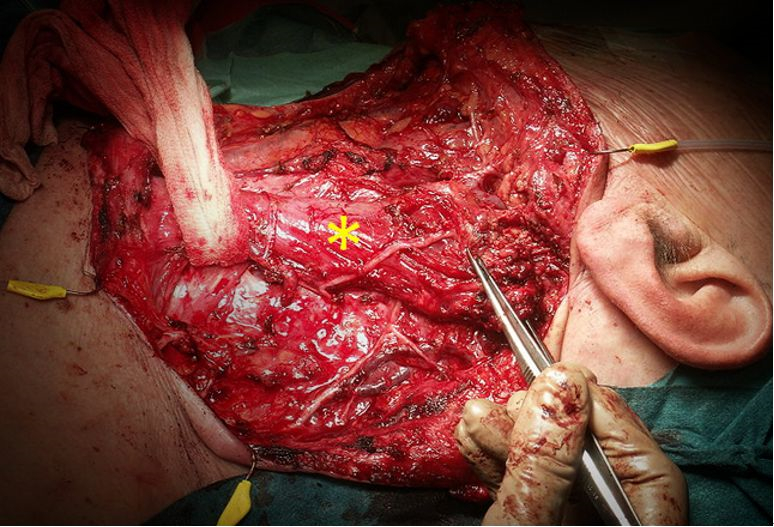

雙側葉甲狀腺癌手術解說